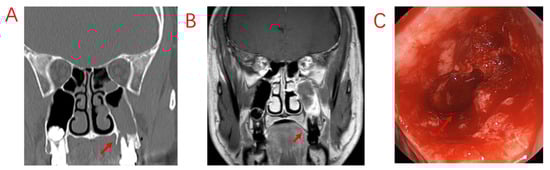

Odontogenic lesions may be caused by dental disease or surgery, implant surgery, or maxillary sinus lift surgery and thus include issues whose etiologies go beyond the etymological definition of “odontogenic”. Although dental implant surgery has caused an increasing number of odontogenic diseases, the vast majority of odontogenic lesions in patients are still caused by typical dental diseases and complications of dental treatment. Among the 103 patients with ODS included in this study, the top three odontogenic etiologies were EPL (49.50%), AP (32.0%), and PE (8.70%); nearly half of the patients presented both apical and periodontal lesions, a share that differed from that reported in previous studies []. This discrepancy may be due to some patients having nonobvious periodontal lesions and being diagnosed with AP or no odontogenic etiology. Both pulpal and periodontal tissue lesions are involved in EPL. In patients affected by PE, EPLs usually progress slowly without important symptoms. The most common signs and symptoms of pulp-infected teeth in EPL are narrow, deep periodontal pockets that reach or approach the root apex and respond negatively to pulp vitality testing []. These symptoms are consistent with those in our patients diagnosed with EPL (Figure 1). According to our analysis, there are two possibilities; the first is chronic necrosis of the pulp, which occurs without considerable pain due to the chronic irritation of the pulp by the filling, resulting in apical lesions. The other possibility is pulpal necrosis due to chronic PE, which may also cause no obvious pain. Since some periapical lesions are too small to be observed on sinus CT, CBCT should be performed to look more closely at dental lesions in patients with a high clinical suspicion of ODS.

Figure 1.

A patient with odontogenic sinusitis due to EPL with bone defects in the MSF. (A): Sinus CT shows resorption of alveolar bone on the palatal side of the left upper first molar, forming a narrow and deep periodontal pocket. (B): MRI shows diseased tissue in the periodontal pocket connected to swollen mucosa in the maxillary sinus. (C): Bone penetration of the palatal MSF in the extraction socket is observed during surgery. Red arrows indicate bony defects in the MSF.